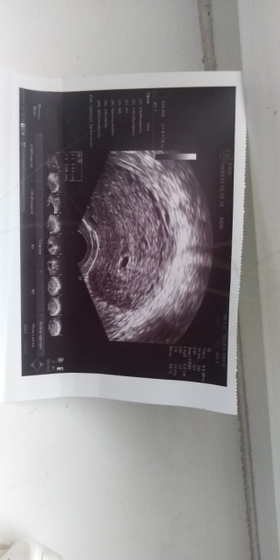

Сделали наконец то сегодня узи плодное яйцо появилось, но эмбрион ещё не увидели((( 3-4 эмбриональные недели всего лишь. Сказали придти через 3 недели. Это все хорошо. Нооооо, сказала что видит ещё очень маленькое точку сказала это типо кровь. Утрожестан сказала продолжать вставлять должно рассосаться. Было у кого нибудь такое? Очень страшно…

У меня в ровно 5 недель (от начала месячных) видно было тоже только бусинку 3,3 мм. И такая ситуация у многих. Я думаю можно наслаждаться беременностью и не переживать ?? На этом сроке главное — это подтверждение маточной Б. А остальное потом ??